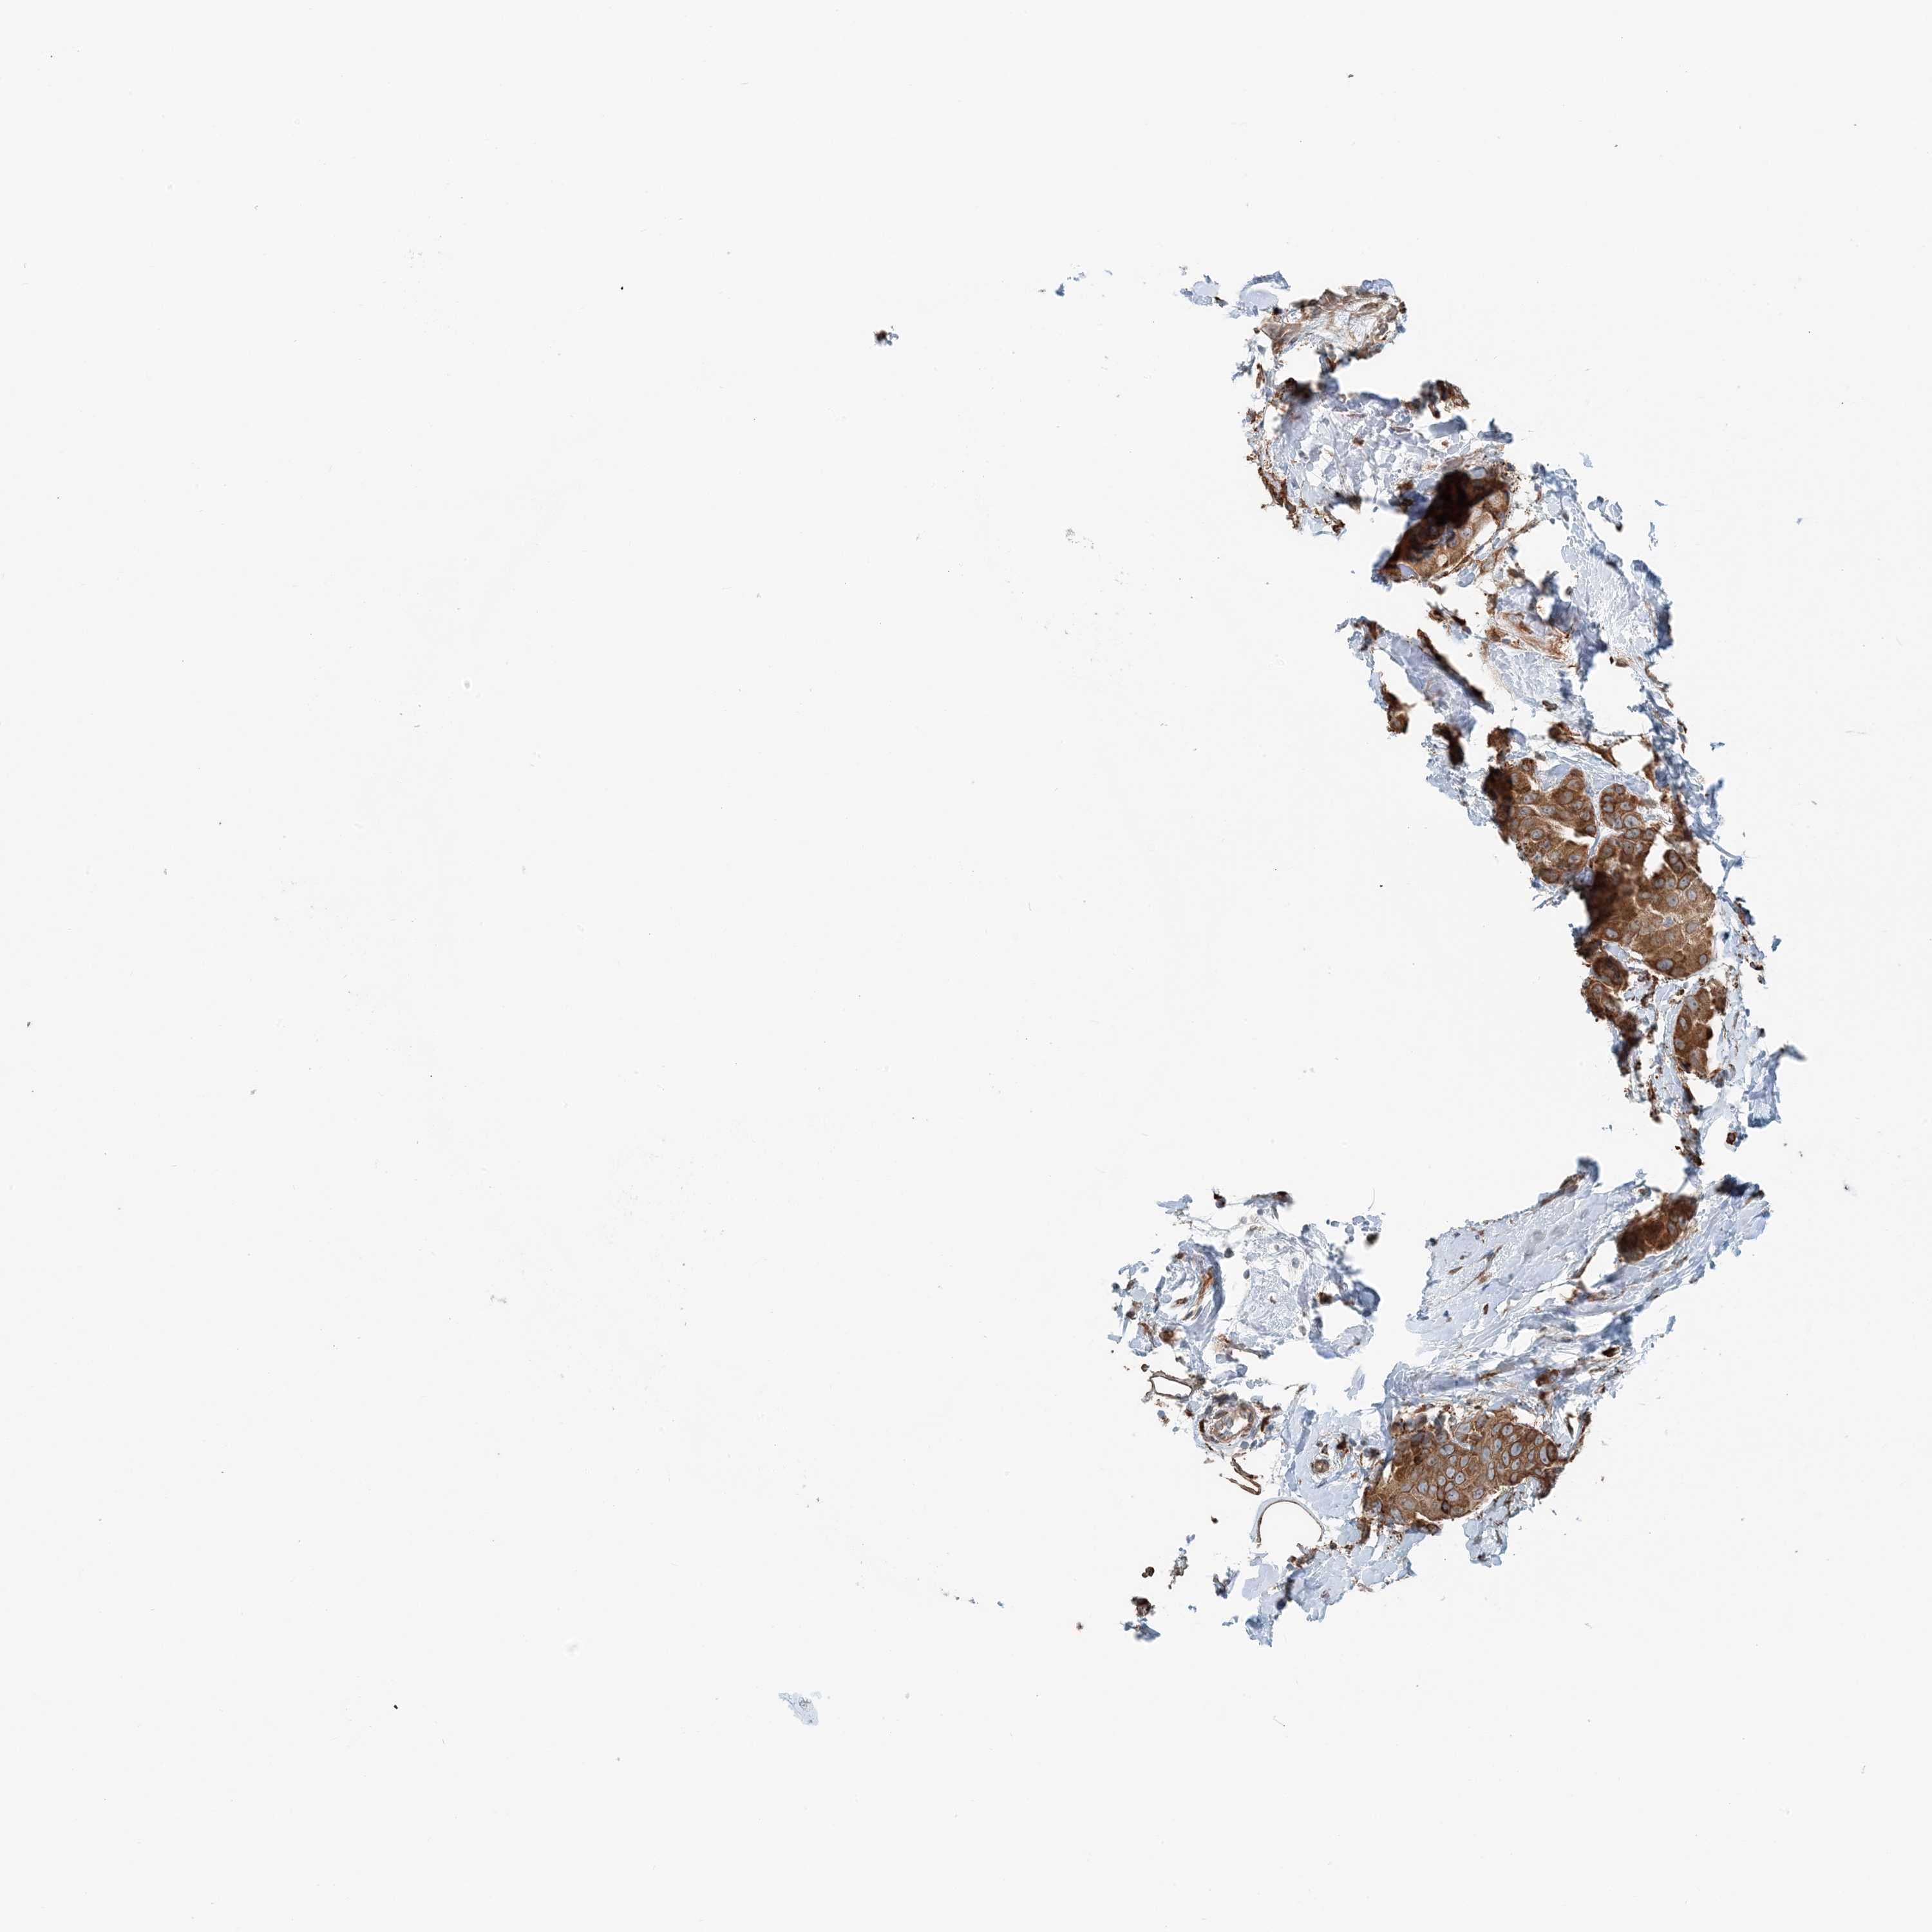

CANCER BREAST CANCER Show tissue menu

BRCA TCGA BRCA VALIDATION PROTEIN EXPRESSION